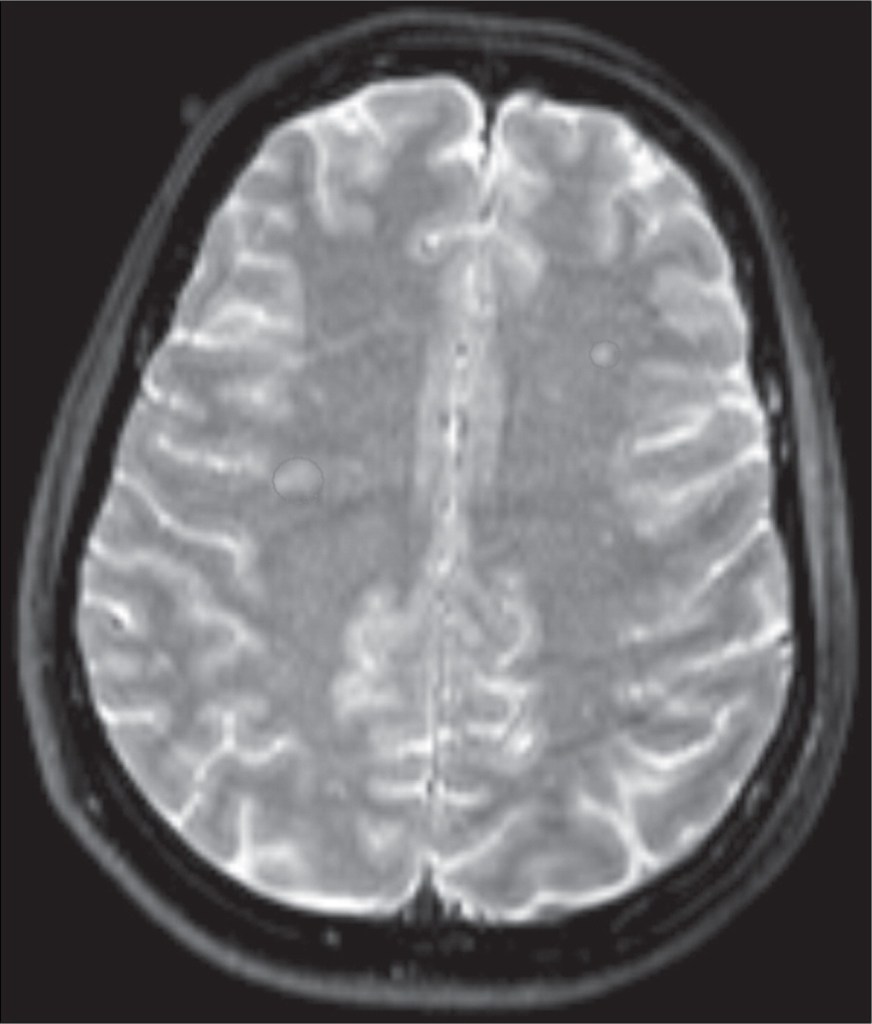

La mujer buscó ayuda médica recién a los 52 años, cuando acudió a una clínica psiquiátrica en La Haya. Al principio, los análisis y exámenes parecían normales: sangre, estudios neurológicos e incluso un EEG no mostraron anomalías significativas. Fue una resonancia magnética la que reveló la clave: pequeñas lesiones en la sustancia blanca cerca del núcleo lentiforme, área crucial para el reconocimiento facial, la memoria y la atención.